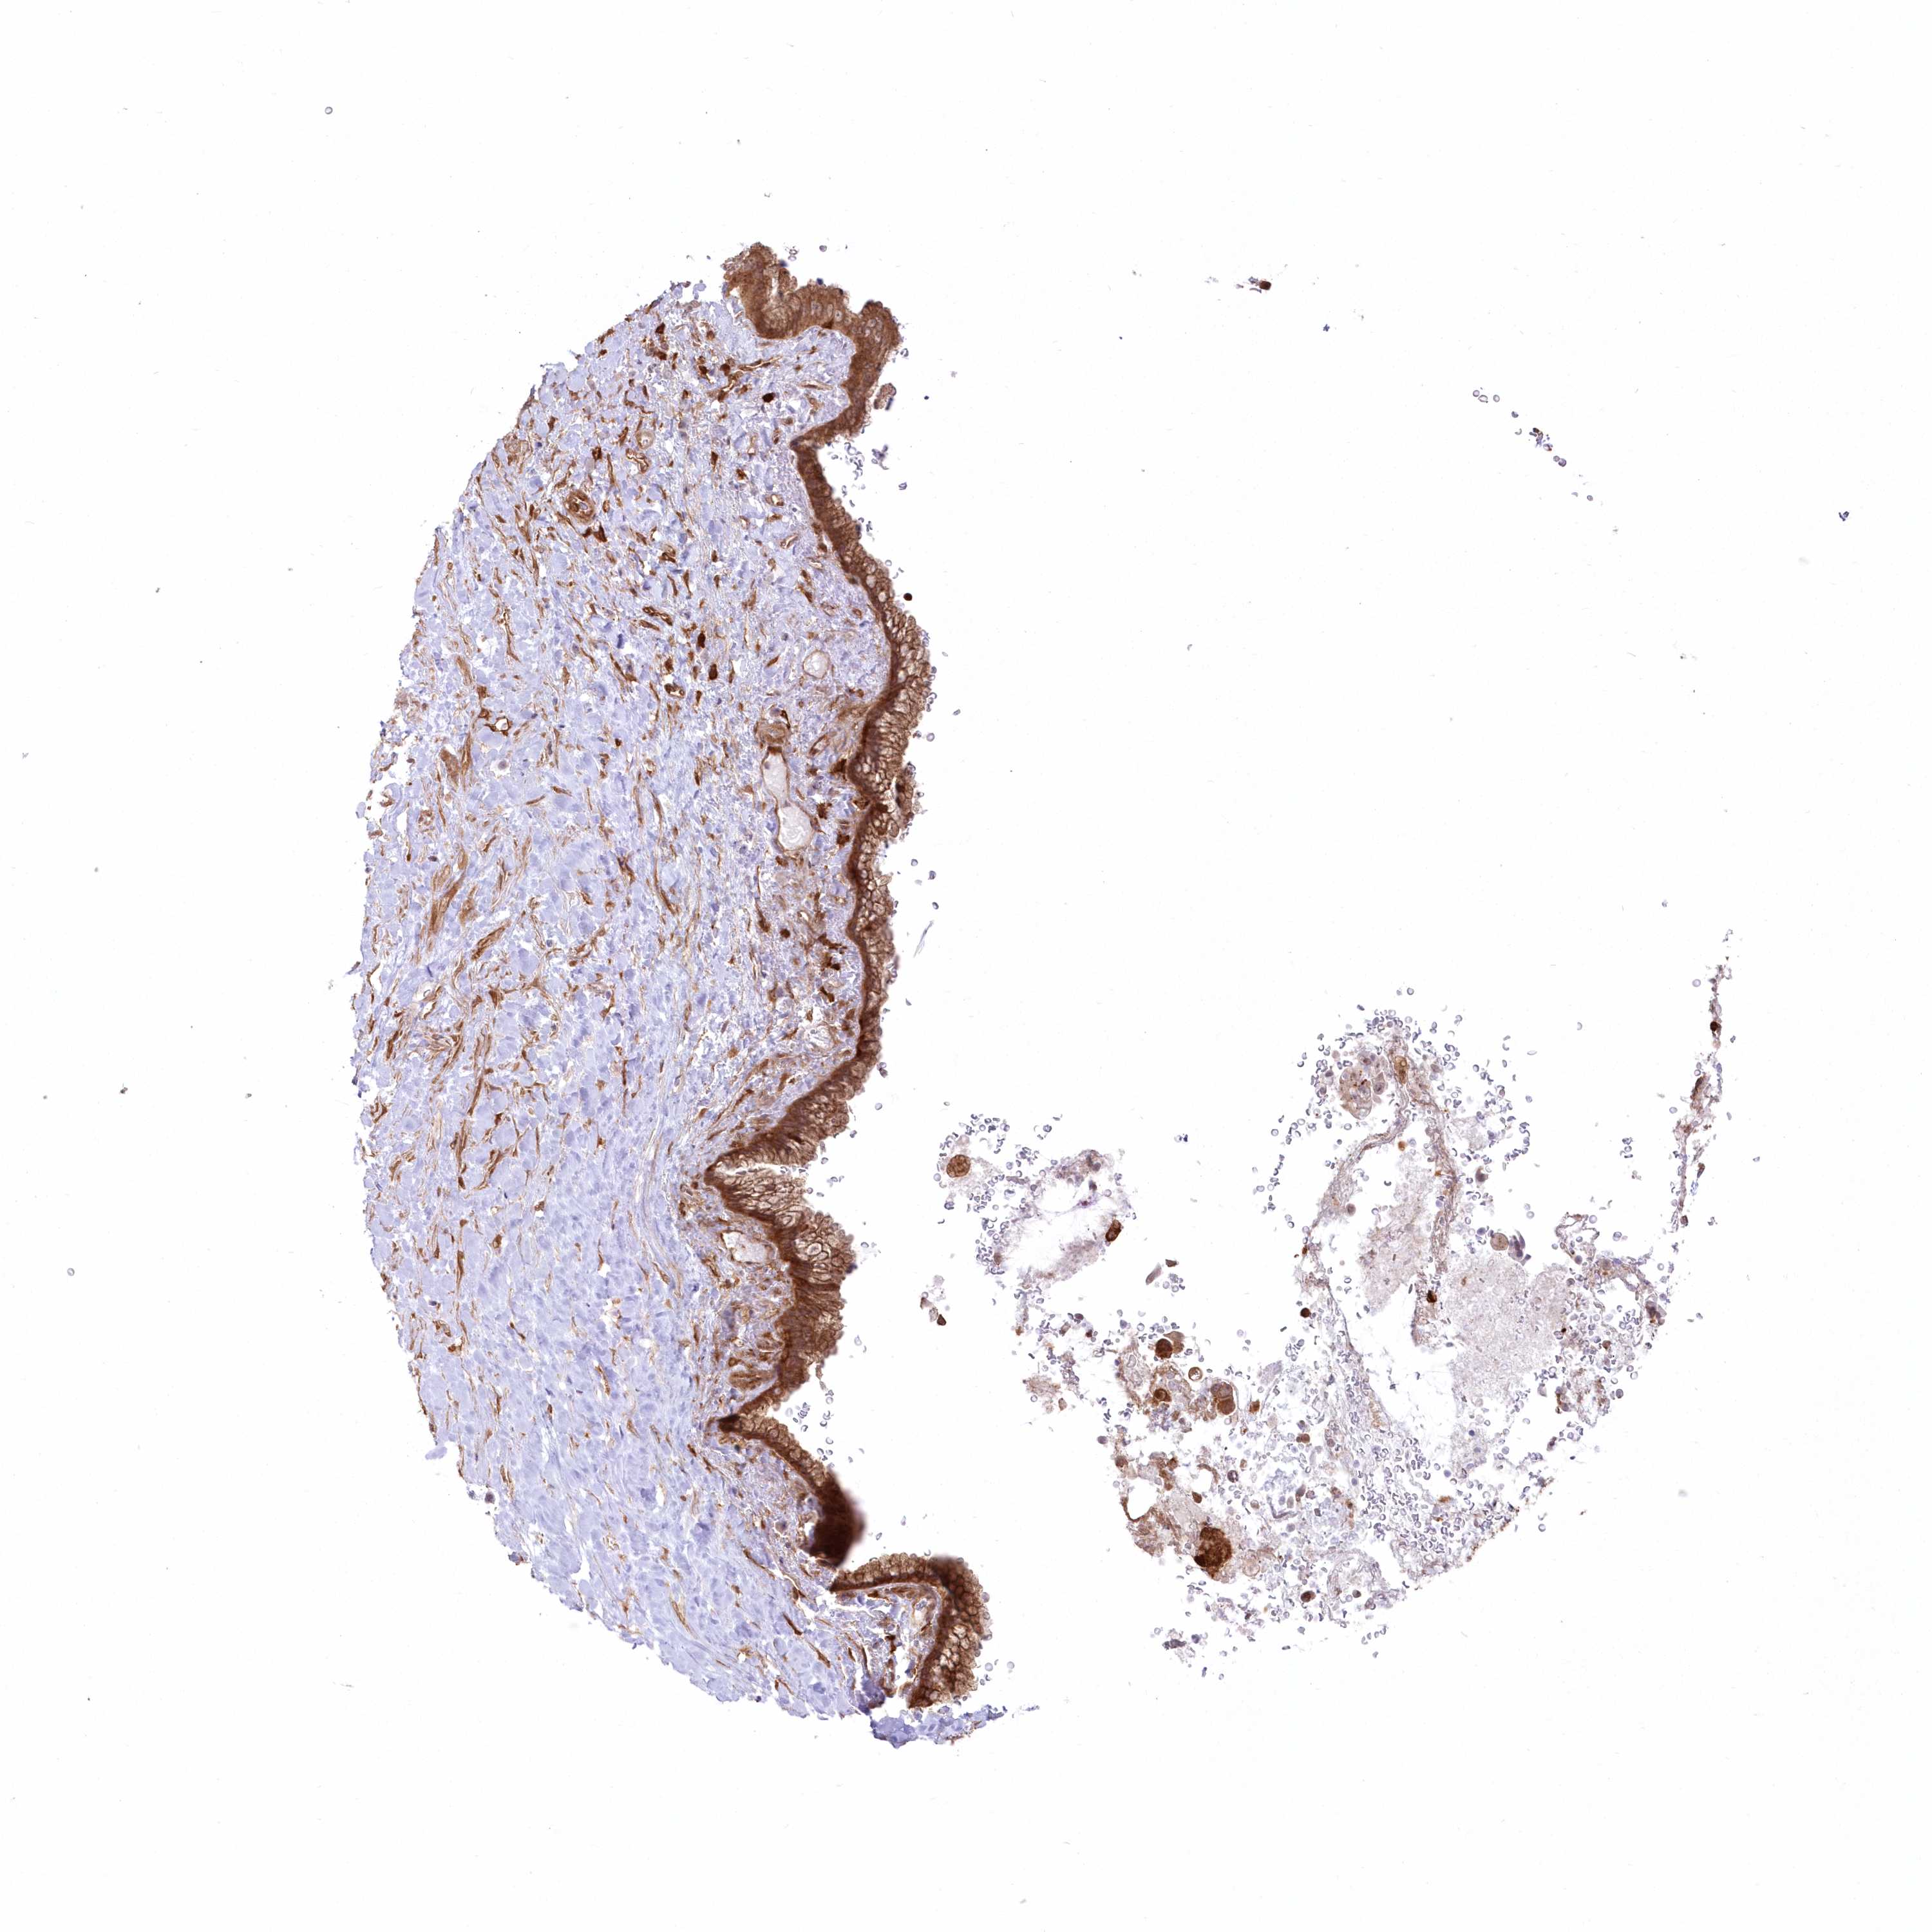

PANCREATIC CANCER - Protein expressioni

A mouse-over function shows sample information and annotation data. Click on an image to view it in a full screen mode. Samples can be filtered based on level of antibody staining by selecting one or several of the following categories: high, medium, low and not detected. The assay and annotation is described here.

Note that samples used for immunohistochemistry by the Human Protein Atlas do not correspond to samples in the TCGA dataset.

Antibody stainingi

Antibody staining in the annotated cell types in the current human tissue is reported as not detected, low, medium, or high, based on conventional immunohistochemistry profiling in selected tissues. This score is based on the combination of the staining intensity and fraction of stained cells.

Each image is clickable and will lead to virtual microscopy that enables deeper exploration of all samples and also displays staining intensity scores, fraction scores and subcellular localization as well as patient and tissue information for each sample.

Antibody HPA036471

Staining

High

Medium

Low

Not detected

Intensity

Strong

Moderate

Weak

Negative

Quantity

>75%

75%-25%

<25%

None

Location

Nuclear

Cytoplasmic/membranous

Cytoplasmic/membranous,nuclear

Adenocarcinoma, NOS